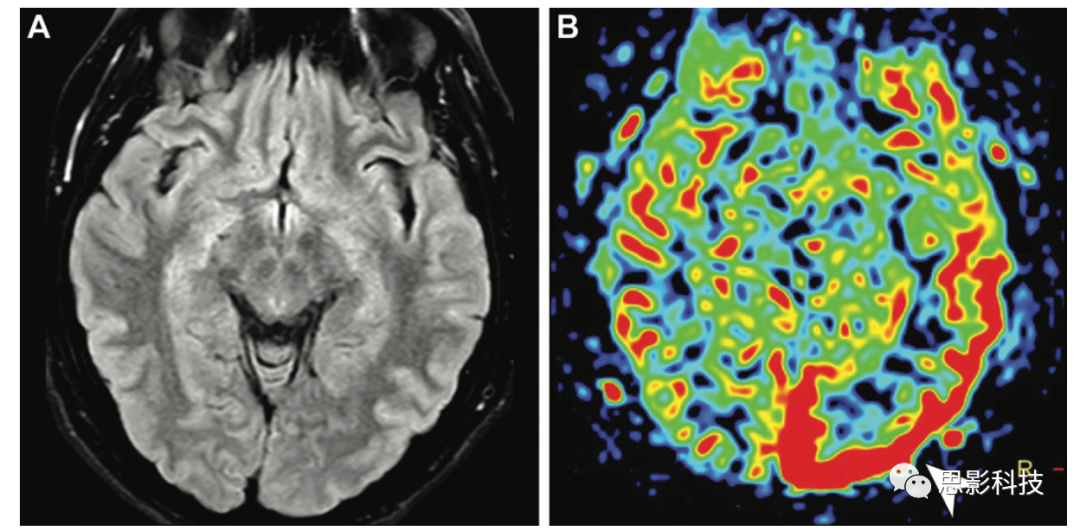

感染 腦膿腫在中腔及周圍水腫區(qū)的ASL信號(hào)降低,邊緣強(qiáng)化的信號(hào)增強(qiáng)(18)。據(jù)報(bào)道,在硬膜外膿腫和其他感染性疾病,如皰疹性腦炎,可能繼發(fā)于靜脈受壓或局部大腦調(diào)節(jié)機(jī)制障礙,顯示皮質(zhì)ASL信號(hào)強(qiáng)度增加。

18 腦膿腫,9歲兒童癲癇發(fā)作5天。(AB)軸位增強(qiáng)T1加權(quán)像(A)和彌散加權(quán)像(B)顯示左側(cè)額葉局灶性病變,呈環(huán)形強(qiáng)化,彌散受限,表明膿腫。(C)ASL MRI顯示病灶核心的低CBF,周圍有水腫。邊緣強(qiáng)化顯示信號(hào)增強(qiáng)。